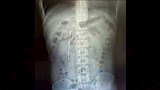

الرجل، ويدعى وانج من مدينة ونتشو بمقاطعة تشجيانج في جنوب شرق الصين، توجه لمستشفى تابع لجامعة ونتشو الطبية بعد شعوره بانزعاج في البطن، حيث أظهر الفحص وجود جسم غريب عالق في الاثني عشر، تبين أنه على الأرجح مقياس حرارة قديم، بحسب موقع ساوث تشاينا مورنينج بوست.

وبحسب الأطباء، فإن وجود الجسم بهذه الطريقة شكل خطرا كبيرا، إذ كان يضغط على جدار الأمعاء، ما قد يؤدي إلى ثقب أو نزيف داخلي خطير.

ورغم خطورة الموقف، تمكن فريق طبي من استخراج الجسم الغريب خلال عملية استغرقت نحو 20 دقيقة فقط، وسط دقة عالية بسبب قرب المقياس من القنوات الصفراوية، ما كان قد يسبب إصابة خطيرة في جدار الأمعاء.

وأكد الأطباء أن المقياس ظل سليما عند إخراجه، رغم تآكل العلامات المرسومة عليه بعد سنوات طويلة داخل الجسم.